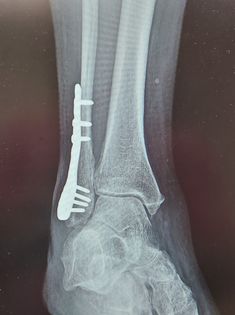

I broke my ankle and leg about two months ago trying to get two hens off my porch. I forgot where I was and fell off some steps. A few screws and one plate later and I’m just now starting to put some weight back on my foot. Be careful out there, little critters can cause some unforeseen accidents. – Michele Taylor